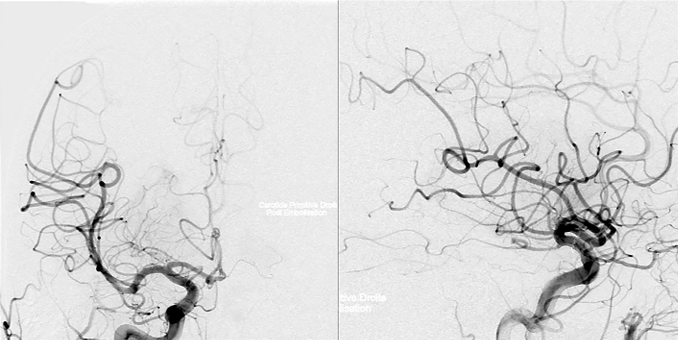

福教授的决策策略是:放弃内镜经鼻入路的选择,转而选择经后岩骨入路的手术方案。这一入路最初由Hakuba等人于1985年提出,主要用于颅咽管瘤的手术治疗过程。由于垂体细胞瘤与垂体漏斗部区域的颅咽管瘤在解剖位置上存在高度相似性特点,这一入路可以提供从后方到前方、从下方到上方、从外侧到内侧的多维度手术视野,能够直接观察肿瘤与周围关键结构的解剖关系状态,有助于从垂体柄的后方区域进入,最大程度地保留垂体功能的完整性,同时增强对穿孔血管的可视化控制程度。此外,该入路引发脑脊液漏并发症风险的概率也相对有限些。

福教授作出的决策是:在手术之前进行血管栓塞处理,切断肿瘤的主要血供来源。血管造影结果显示,栓塞后的肿瘤供血动脉重建率达到了百分之九十的水平,栓塞线圈在垂体上动脉内部清晰可见。这一关键步骤为后续的手术操作奠定了安全的血流控制基础——整个手术过程中没有出现任何明显的出血状况及相关并发症的发生。